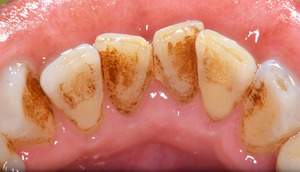

歯石除去

治療前

治療後

| 年齢 | 36歳・男性 |

| 主訴 | 歯石をとりたい |

| 治療内容 | 歯石除去 |

| 治療期間 | 30分 |

| 費用 | 約2,000円 |

| リスク・副作用 | ・歯ぐきの炎症が強いと歯石を取る際に出血することがあります。 ・処置後に歯がしみることがあります。 ・歯と歯の間に隙間ができるので、息が漏れ発音しにくいと感じることがあります。 ・歯ぐきの炎症が軽減すると歯ぐきが引き締まり、歯が長く見えることがあります。 |